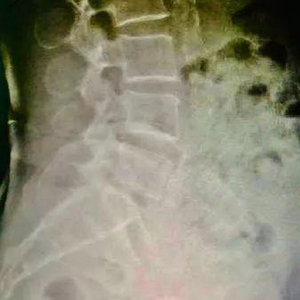

三维重建显示阿婆断针的位置

确定针的位置后,潘裕国迅速为阿婆施行介入手术,通过垂直面向下切开2厘米,成功将断针从腹中取出。随后,医生还给梁阿婆打了破伤风针。目前,梁阿婆已平安出院。但由于针扎的位置就在包块处,阿婆的感染可能要面临更久的愈合期。